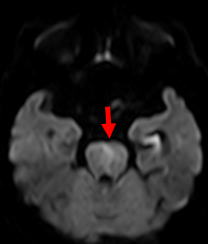

脳梗塞は発症してもすぐにCTやMRIで所見が出るわけではありません。最も感度の良い「拡散強調画像」という特殊な検査法でも、発症から約30分から1時間ほど経たないと異常は発見できません。従って、ごく早期の脳梗塞は「脳卒中の症状があり、CTで出血がなければ脳梗塞」と診断するわけです。また、CTでは診断に限界がある場合も多く、MRI検査が必要です。当院では症状のある患者さんは最優先にMRI検査(24時間稼働)をしております。(図1)

図1:脳梗塞のMRI拡散強調画像。矢印の部位が淡く白くなっています。 |